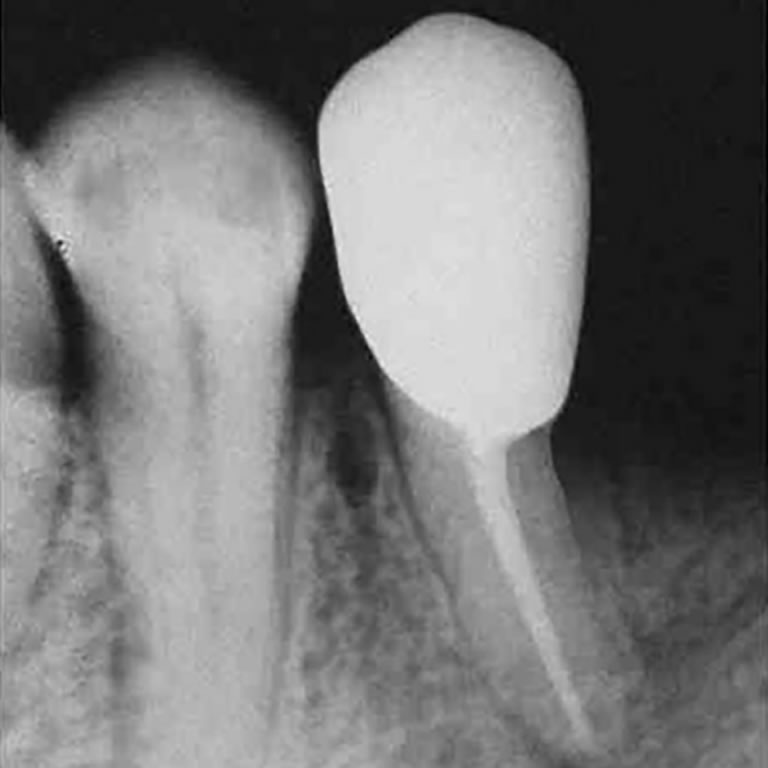

Endodoncia o Implante

Prof. Dr. Fernando Goldberg

El texto compara endodoncia e implantología, resaltando que la endodoncia es un tratamiento preventivo que preserva el periodonto y evita la reabsorción ósea asociada a la extracción dentaria y a los implantes, ayudando a mantener la estructura ósea perirradicular.